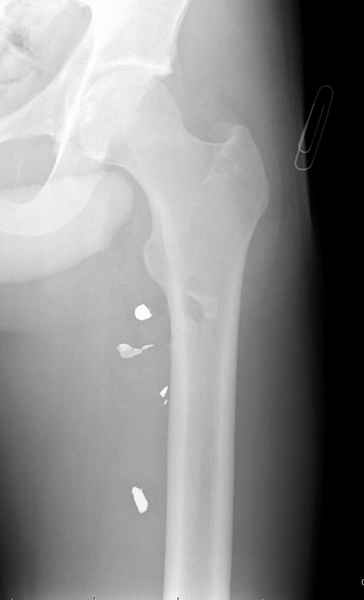

Больной с огнестрельным переломом бедра с вовлечением около 15% медиального кортекса, входное отверстие около 1 см в диаметре; стабильный, без сосудистых и неврологических признаков.

Литературные данные о влиянии кортикального дефекта на стрессовые переломы в длинных трубчатых костях в основном встречаются в онкологии, например кортикальный дефект более 50% имеет больше шанса стрессовых переломов, чем в нашем случае.

Учитывая, что больной получил травму не во время визита в церковь, и он является одним из представителем 40 миллионного “outstanding itizen”, без медицинской страховки, без работы в свои 39 лет, и без надлежающей ортопедической дисциплины у которого отсутсвует страх стрессового перелома, было рекомендовано оперативное лечение: профилактическое антеградное интрамедуллярное штифтование.